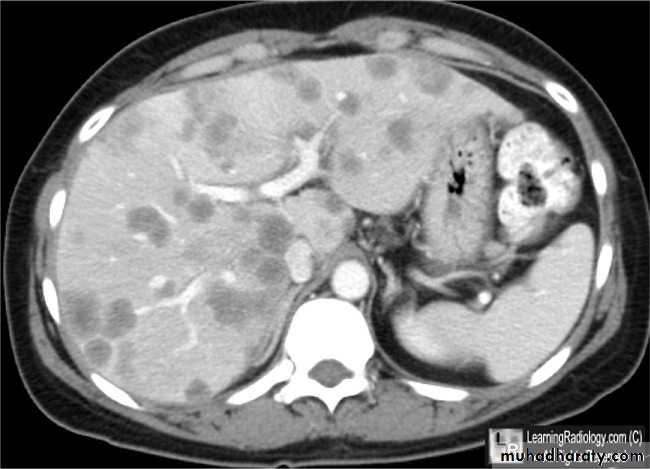

Secondary metastasis in the liver

Multiple rounded hypo density areas of different density , shape & different size .

Pattern of enhancement is either uniform , target or bulls eye pattern .

Hepato megaly .

Secondary metastasis within the liver

CT Scane